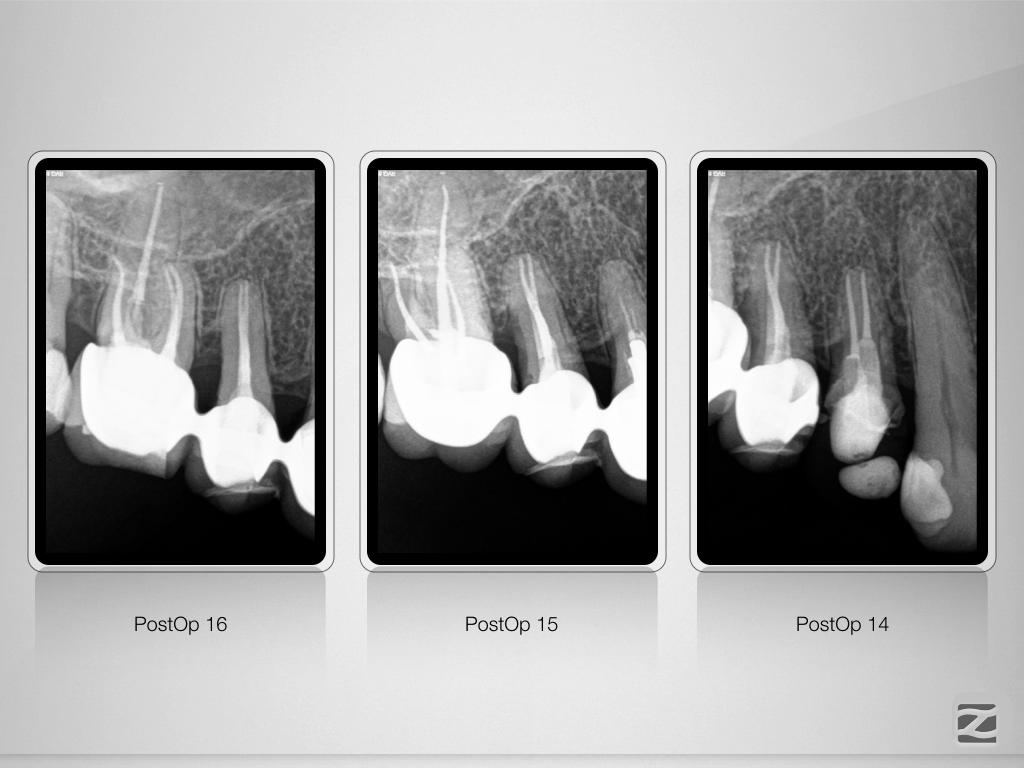

16-14D.010

Mein endodontischer Alltag